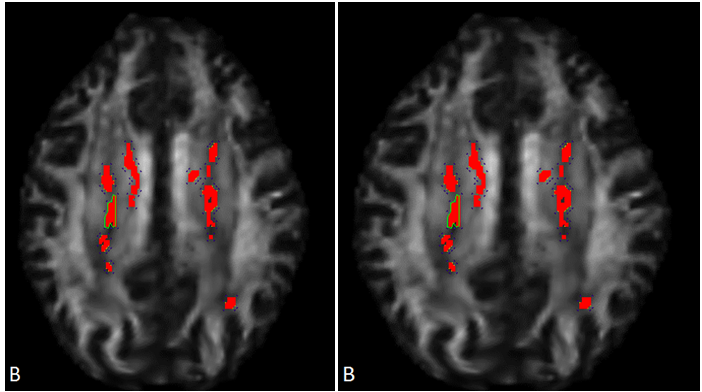

MRI-DTI analysis

Brain imaging assessments done with MRI Diffusion Tensor Imaging show significant abnormalities consistent with traumatic brain injury and high risk of chronic traumatic encephalopathy (Figure 4a). MRI-DTI findings found that the defendant displays very significant abnormal decreases in FA in the left anterior corpus callosum (mean FA ROI ratio is 0.37 whereas controls averaged 0.58, standard deviation=0.04, z-score= -5.38, p-score =, 7.6E-08). The decrease in FA in the mid corpus callosum is consistent with significant and multiple TBIs received in the past. He also has very significant abnormal decreases in the left internal capsule FA (mean FA is 0.25 whereas controls averaged 0.42, standard deviation = 0.02, z-score =-7.91, p-score =2.5E-15 (Figure 4b). The odds of this occurring by chance alone are 2.5 out of quadrillion.

Figure 4A, MRI-DTI findings found that the defendant displays very significant abnormal decreases in FA in the left anterior corpus callosum. B, Diffusion Tensor Imaging (DTI) Statistical Analysis. Left anterior corpus callosum and left internal capsule display high risk of CTE. Abnormal decrease in fractional anisotropy (FA) in left internal capsule consistent with traumatic brain injury. P-value 2.5E-15, indicated the chances of this occurring by chance is 2.5 out of a quadrillion.

Other MRI findings

There are punctate T2 and inversion recovery hyperintensities in the left frontal periventricular white matter identified. These are nonspecific but can be seen in cases of axonal shearing from brain trauma as well as microvascular disease. There are no focal or diffuse signal abnormalities on the axial DWI imaging (Figure 6). The SWI-venous bold images are remarkable for a punctate area of signal abnormality in the left frontal periventricular white matter which may reflect blood product and/or hemosiderin deposition. The DTI- Tractography images demonstrate some thinning of the corona radiata fiber tracts bilaterally.